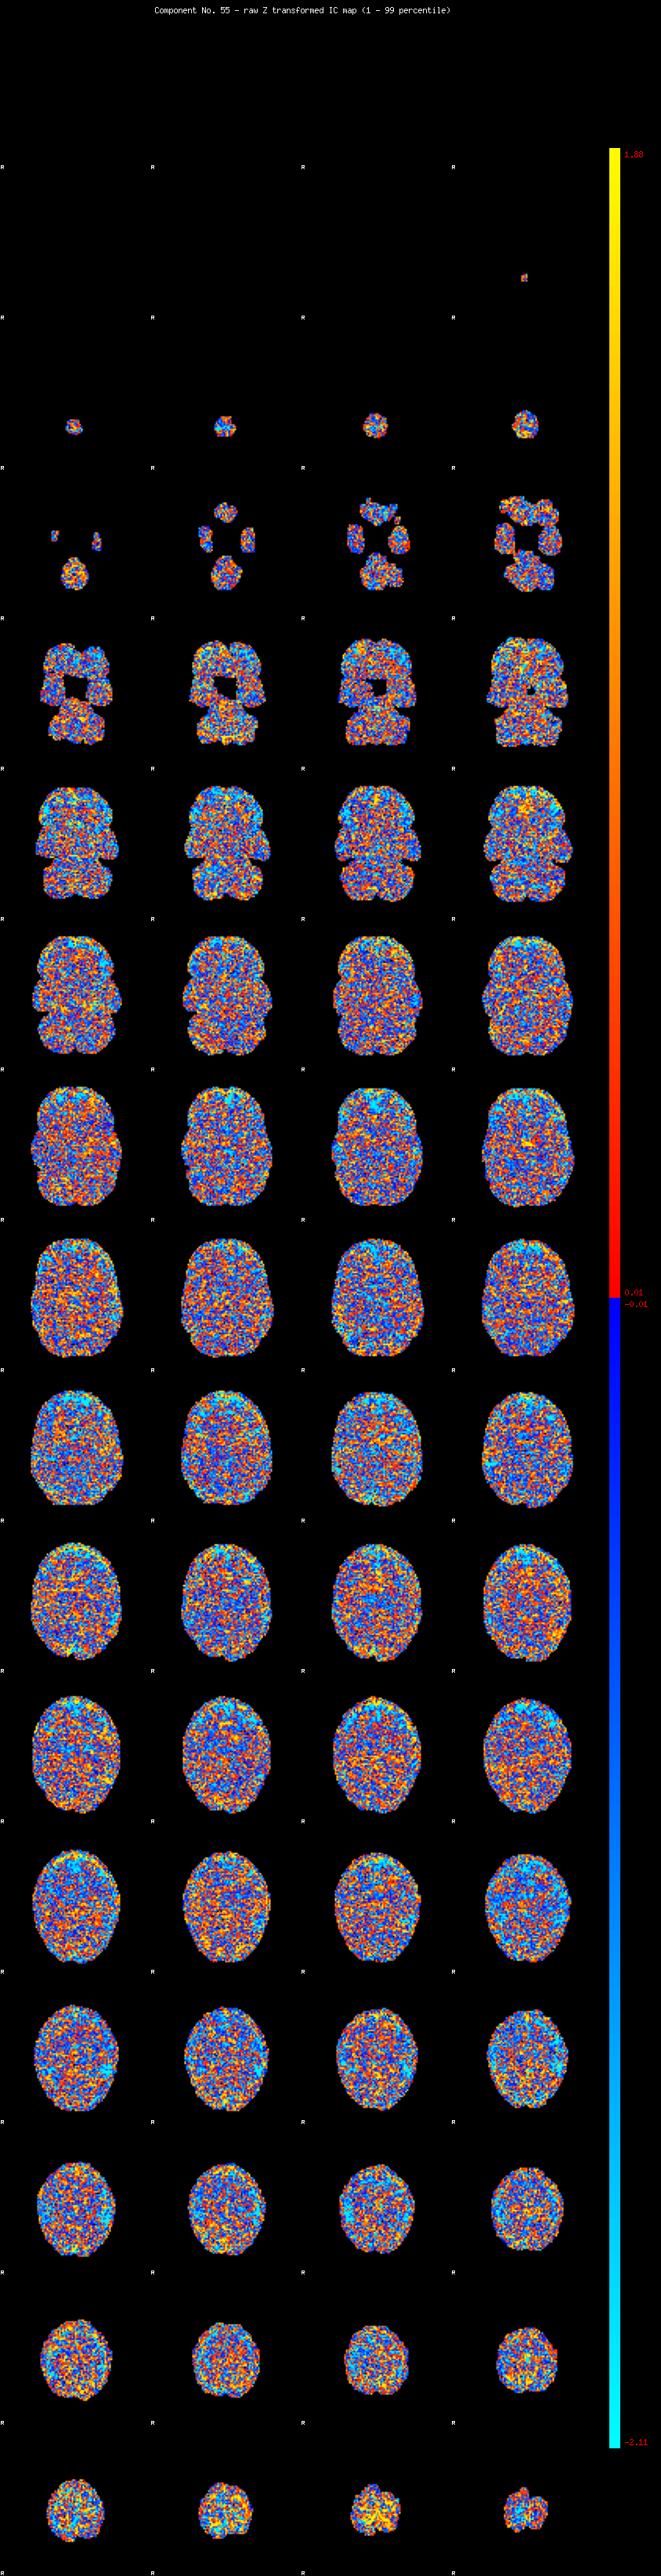

IC_55 Mixture Model fit

Means : -0.000000 2.266444 -2.231694

Vars : 1.000000 0.746183 1.208204

Prop. : 0.926658 0.021515 0.051826